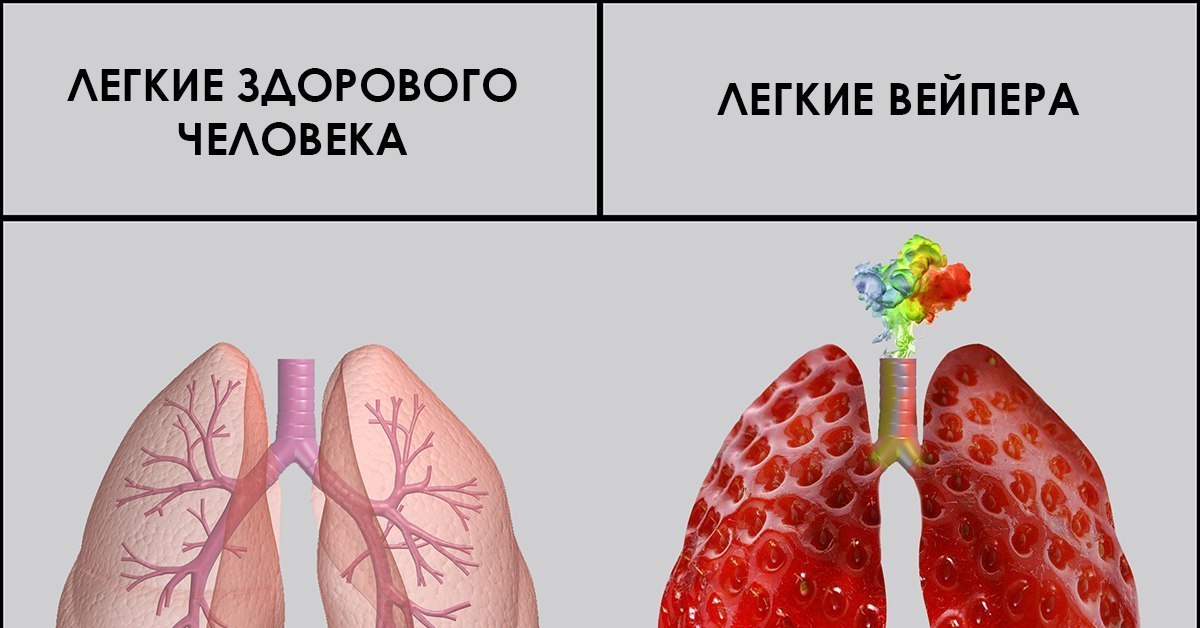

Здоровые Легкие Картинки

Здоровые Легкие Картинки 117 фото